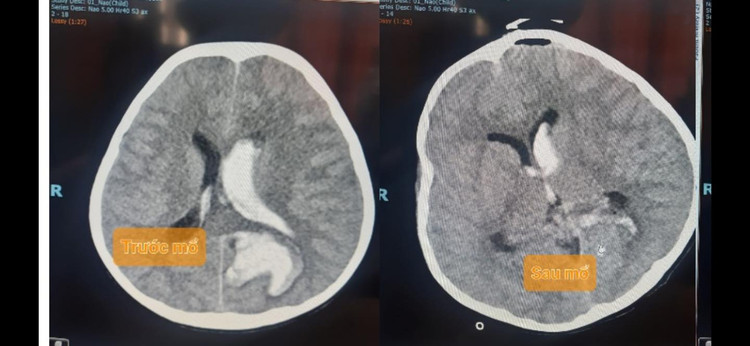

Cả 3 bé gái đều đột ngột hôn mê trước khi vào viện, 2 bé gái sinh năm 2013 N.T.H.Y và N.H.H.Y, 1 bé sinh năm 2017 T.N.N.H. Cả 3 cháu bé đều được chụp CT scan sọ có thuốc phát hiện có một búi dị dạng đường kính 2 X 3 cm ở thuỳ thái dương, thuỳ chẩm và thùy trán gây xuất huyết não – não thất.

3 bệnh nhi được tiến hành phẫu thuật mở sọ lấy máu tụ và bóc lấy toàn bộ búi dị dạng. Tình trạng sau mổ các cháu tỉnh táo, vết mổ lành tốt.

| Hình ảnh phim chụp não của bệnh nhi - ảnh BVCC |